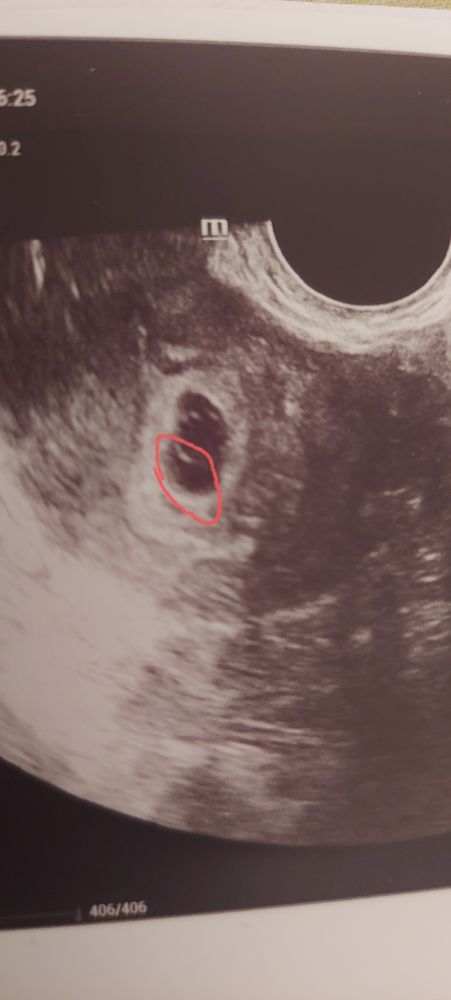

Что это за нарост в плодном яйце?

Нароста здесь никакого нет. Если только начинающаяся отслойка. У вас очень маленькое ПЯ и большой желточный мешок 5.7мм для вашего срока. Это плохой знак. Надо готовиться ко всяким исходам событий.

Вот прям под жм.границы пя в этом месте не четкиеИзображение

В лодном яйце по самому краю, под желточным мешком

Maria, плодное яйцо - это черное пространство и кроме ЖМ там ничего не просматривается. На мой взгляд, для ПЯ 14 мм ЖМ слишком велик. Какой размер ЖМ вам написали?

Он должен быть внутри. Какой размер плодного яйца?

Татьяна, 14 мм